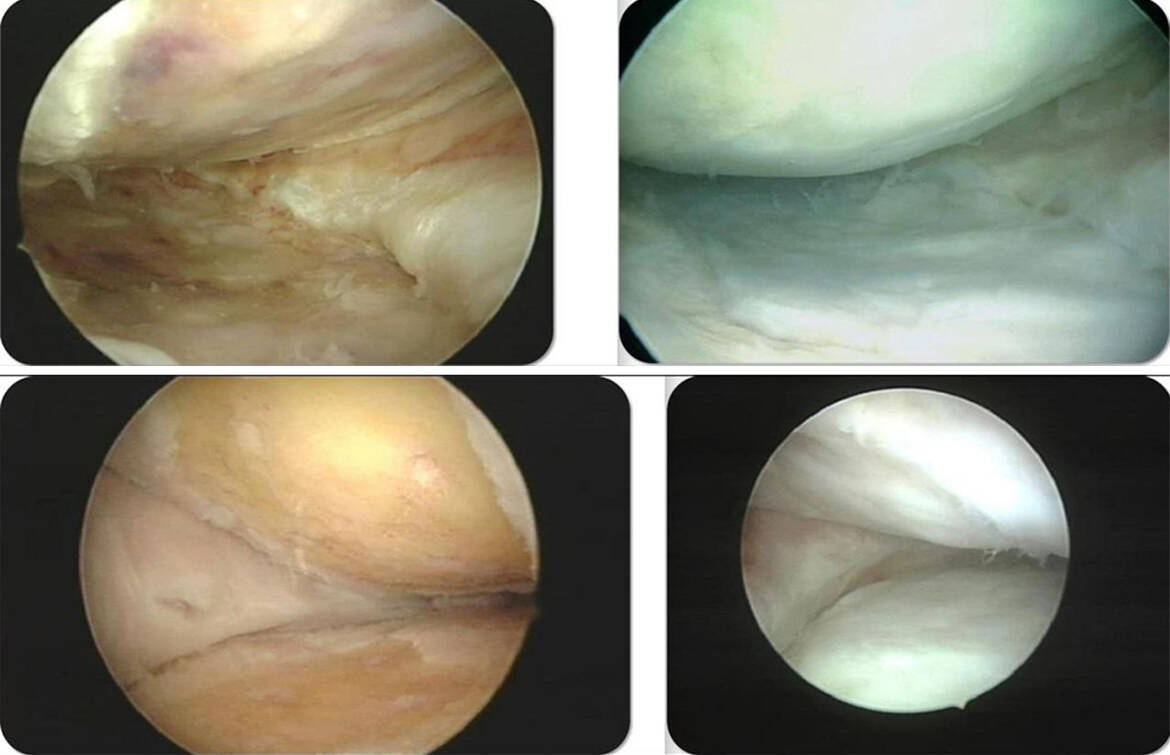

Также им созданы специальные тонкие эндоскопы. Их диаметр – всего 2 миллиметра, тогда как обычно они в четыре раза больше. Чтобы сделать хирургический доступ обычным эндоскопом, нужно сделать разрез около полутора сантиметров. Двухмиллиметровый эндоскоп вводится только проколом через расширители без разреза, благодаря чему у пациента не остается операционных ран.

«Я всегда стремился лечить натуральным образом, а не прибегать к протезированию. Уверен, что замена – это капитуляция. В чем суть нашей технологии? В пораженном месте мы специальными инструментами делаем микропроколы. Получается, что мы специально наносим небольшие повреждения, чтобы запустить новый кровоток и процесс регенерации. Также мы заведомо берём у человека жировую ткань и кровь, из которых извлекаем концентрат регенеративного комплекса клеток и веществ, который пересаживаем в поврежденное место. Пересаженные клетки, новый кровоток и новые специальные повреждения начинают построение новых тканей, регенеративно реконструируя структуры», – объяснил доктор.